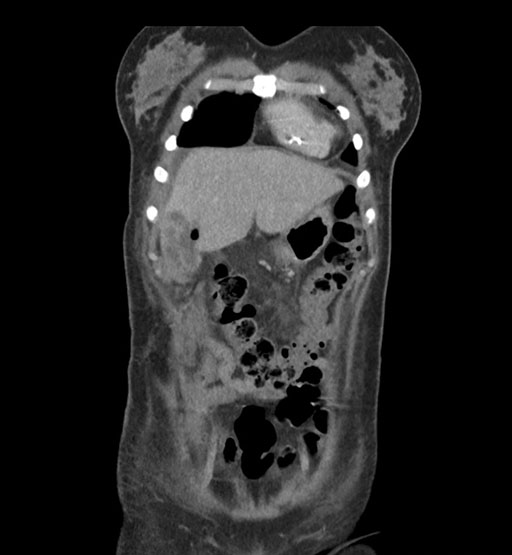

Vasculobiliary injury [M28]

Imaging Analysis

Look through the patient's CT scan to identify any areas of concern for the necessary procedure.

Coronal Arterial